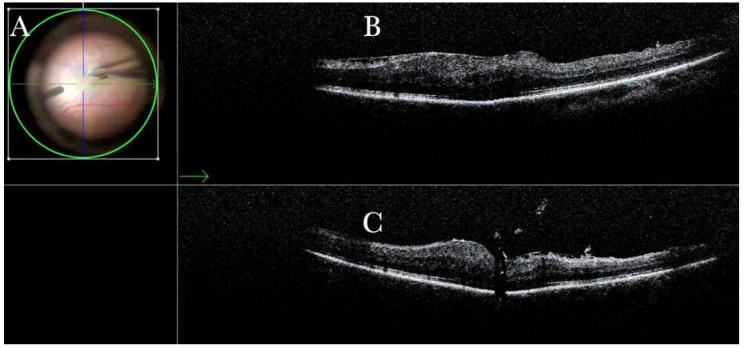

术中光学相干断层扫描在实际玻璃体视网膜手术中的作用

The Role of the Intraoperative Optical Coherence Tomography for Vitreoretinal Surgery in a Real-Life Setting.

To descriptively report the advantages and the feasibility of microscope-integrated intraoperative optical coherence tomography (i-OCT) in managing different vitreoretinal diseases in a real-life setting.

METHODS

We conducted an observational retrospective study involving 265 eyes that underwent elective retinal surgery and intraoperative OCT between 1 September 2018 and 1 October 2022 at Eyecare Clinic (Brescia, Italy).

RESULTS

52 epiretinal membranes, 30 retinal detachments, 60 high myopic eyes, 30 choroidal transplants, 40 macular holes, and 32 vitreo-proliferative retinopathies underwent vitreoretinal surgery and intraoperative OCT scans. The i-OCT was a useful diagnostic exam for all cases and significantly influenced our surgical management.

CONCLUSIONS

i-OCT is a helpful surgical tool in ophthalmic surgery as it provides real-time feedback of tissue anatomy to surgeons, thereby guiding decision-making. Moreover, it provides additional information on the microarchitectural changes after instrument-tissue interactions, further guiding procedures when necessary and possibly reducing unessential surgical maneuvers.